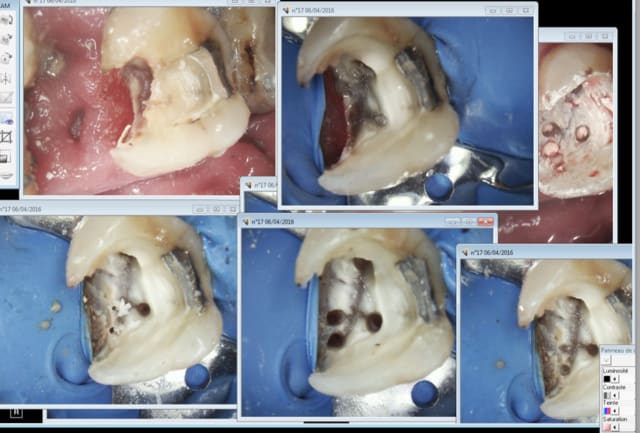

Tu vois moi aucune formation en endo ( en dehors de ma formation initiale mais qui n'est pas Roumaine par contre) , je ne fais que des merdes je roule en Porsche et je n'ai aucun souci. -)

A propos de l'endo c'est plus rapide en rotation continue à fond sur un contre angle bague bleue.